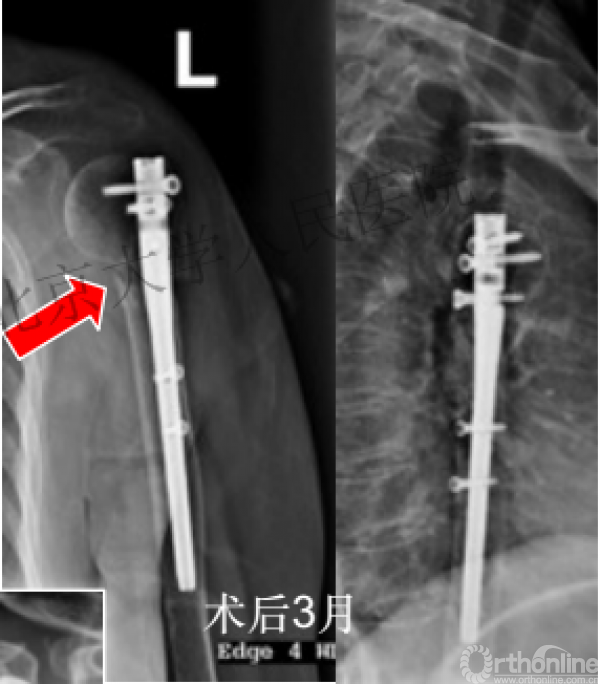

术后3月随访:继发性颈干角变小22°(5-82),肱骨头内翻,达46%

严重影响了患者的生活质量